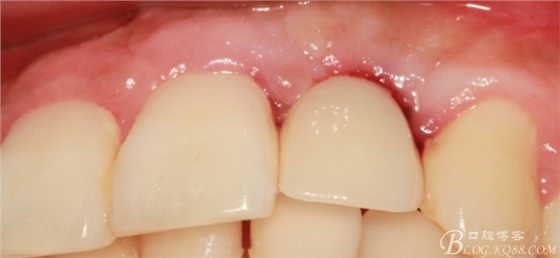

4個(gè)月后,唇側(cè)豐滿度尚可,與鄰牙之間齦乳頭完整。

戴入永久修復(fù)體當(dāng)天口內(nèi)照,雖有小瑕疵,但患者很滿意。